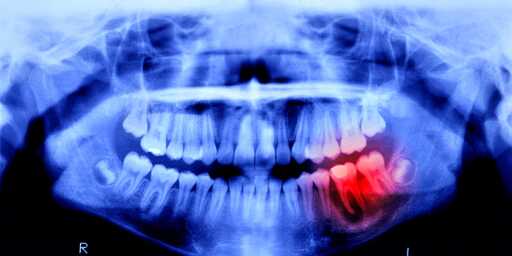

You can pretty much die from bad teeth, like rot and cavities. It is just a matter of when.

A tooth infection can easily spread to your brain and kill you. It’s a very short path.

doesnt need to spread to your brain, just cause sepsis lowering your blood pressure to dangerous levels, or to a major organ and kill you that way.